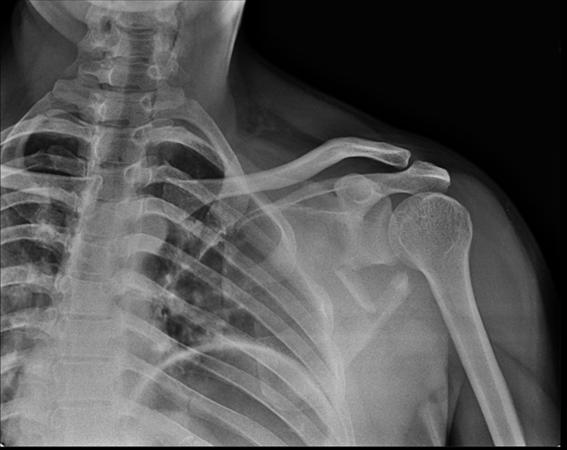

Imaging

• Radiographs

• recommended views

• true AP, scapular Y and axillary lateral view